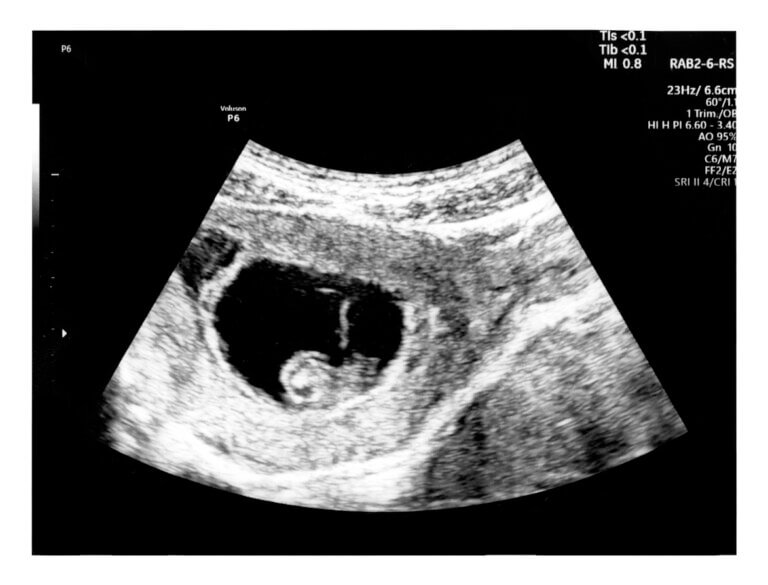

6 week pregnancy ultrasound. SMALL SAC? YouTube . SSW 6+0 bis SSW 6+6 bilden zusammen die sechste Schwangerschaftswoche Bedingt durch die Schwangerschaftshormone lockern und dehnen sich deine Muskeln und Bänder, was zu diesen Symptomen führen kann

Source: ldabrophecl.pages.dev Ultraschall, 6+0 bis 8+0 SSW frauenarztmertens.de , Über 50 Prozent aller Schwangerschaften mit leichten Blutungen im ersten Schwangerschaftsdrittel entwickeln sich ungestört weiter Bedingt durch die Schwangerschaftshormone lockern und dehnen sich deine Muskeln und Bänder, was zu diesen Symptomen führen kann